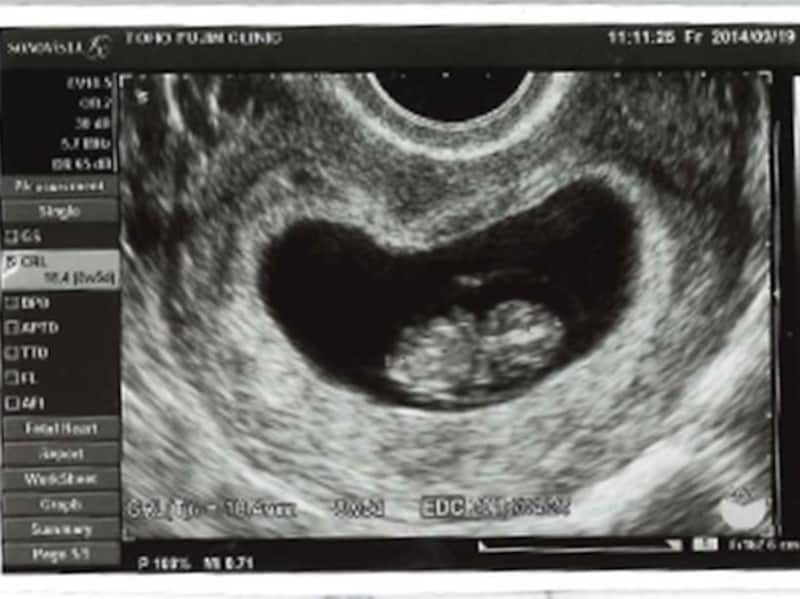

妊娠8週目(8w)には、頭殿長(座高)が15~20mmほどになり、「胎芽」から「胎児」と呼ばれるように。まだ小さいですが、心臓、脳、肝臓、肺、腎臓などの、ほとんどの内臓の基本的な形はすでにできあがっています。

超音波検査では、人間のミニチュアのように見えてきます。胎児の大きさにまだ個人差がないので、この時期の頭殿長から、出産予定日を再評価し、必要があれば予定日を修正します。